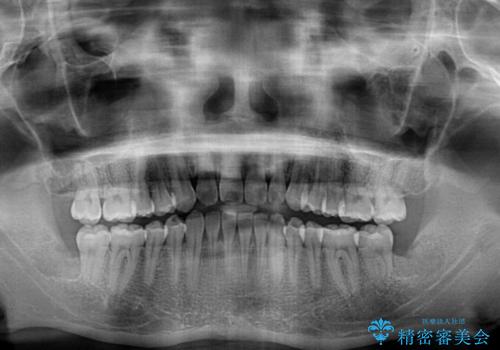

下顎前歯と上顎の部分矯正

- 上下の前歯の叢生を気にして来院された患者様です。

前歯のみの矯正治療を希望でしたが、上顎臼歯が舌側転位していたため、上顎は全体を、下顎は前歯のみを矯正治療することとしました。

矯正治療は上下全顎を行うことが大前提ですが、費用などの点から、今回は部分矯正を選択することとなりました。

患者様本人は咬みにくさを感じていないようですが、部分矯正は咬み合わせの改善が困難であることが多く、咬みにくさが残ることがあります。